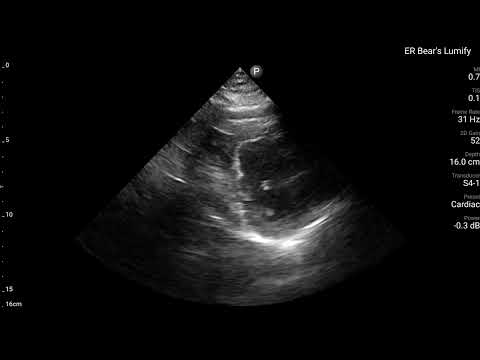

當下有幫病患做echo,讓我們來看看echo有哪些findings?

藉由echo,我們可以看到,LAD支配的Ant.wall幾乎不太動。(請搭配Fig.4安心服用)

ECG在LAD支配位置的Precordial leads出現Subtle STE/PRWP/HATW/此外10分鐘後的dynamic STTC,另外加上echo看到ant.wall有RWMA。這些證據不管怎麼樣都實實在在說明,LAD出現問題了。